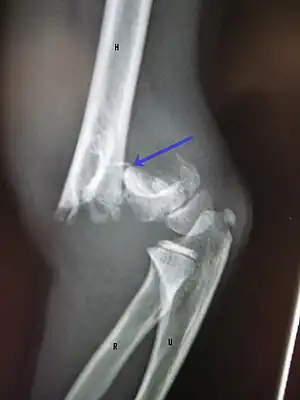

Distal humerus fractures usually occur as a result of physical trauma to the elbow region. If the elbow is bent during the trauma, then the olecranon is driven upward, producing a T- or Y-shaped fracture or displacing one of the condyles.[7]

A displaced supracondylar fracture in a child

Fractures of the humerus are classified based on the location of the fracture and then by the type of fracture. There are three locations that humerus fractures occur: at the proximal location, which is the top of the humerus near the shoulder, in the middle, which is at the shaft of the humerus, and the distal location, which is the bottom of the humerus near the elbow.[9] Proximal fractures are classified into one of four types of fractures based on the displacement of the greater tubercle, the lesser tubercle, the surgical neck, and the anatomical neck, which are the four parts of the proximal humerus, with fracture displacement being defined as at least one centimeter of separation or an angulation greater than 45 degrees. One-part fractures involve no displacement of any parts of the humerus, two-part fractures have one part displaced relative to the other three; three-part fractures have two displaced fragments, and four-part fractures have all fragments displaced from each other.[13][14][3] Fractures of the humerus shaft are subdivided into transverse fractures, spiral fractures, "butterfly" fractures, which are a combination of transverse and spiral fractures, and pathological fractures, which are fractures caused by medical conditions.[12] Distal fractures are split between supracondylar fractures, which are transverse fractures above the two condyles at the bottom of the humerus, and intercondylar fractures, which involve a T- or Y-shaped fracture that splits the condyles.[7]